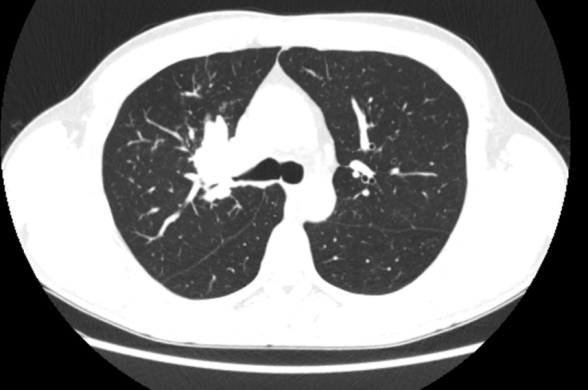

未经过治疗前

经过2周治疗后,肺门的病灶缩小

2周期后复查见右上肺病灶缩小明显,但是2、4组的淋巴结和右侧心膈角淋巴结也没有变化。这种情况考虑治疗部分有效,原发灶CR,2、4组淋巴结无效有可能是治疗周期不够引起。